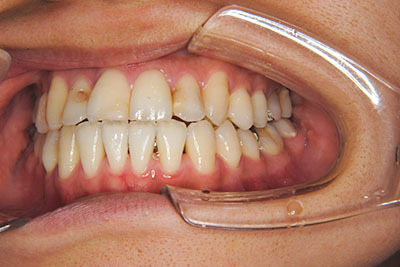

おとなの方でも矯正治療をあきらめないでください!

いくら歯が動き易くとも、本人がやる気でなければ効果は出ませんし、むし歯発生のリスクも高まります。おとなの方は顎の成長が終わっているため、治療の計画が立てやすいとも言えます。「もう大人だから…」とあきらめず、一度ご相談ください。